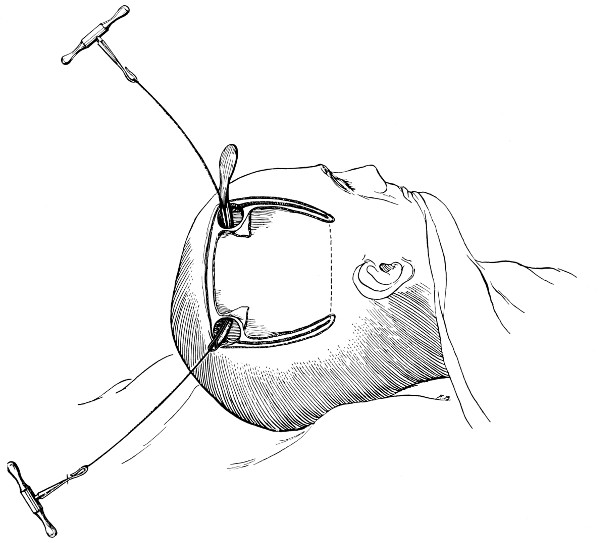

Fig. 17. First Stage in the Formation of an Osteoplastic Flap. Gigli’s saw, protected from the dura mater by the special director, passing between the two trephine-holes. For further description, see text.

Fig. 18. Second Stage in the Formation of an Osteoplastic Flap. The bone-flap turned down and the dura mater exposed.

Fig. 19. Third Stage in the Formation of an Osteoplastic Flap. The dural flap turned down and the brain exposed. Note the relation of the scalp, bone, and dural incisions to one another.

Between these two trephine-holes the dura mater is separated from the bone and the special director introduced, entering at the one hole, emerging at the other, and lying throughout between the dura and the bone. The saw is now passed along the groove of the director, the handles affixed, and the bone intervening between the two trephine-holes divided, not straight out to the surface, but bevelled or cut in such an oblique manner that the bone-flap, when replaced, rests on a ledge (see Figs. 17-19). The sawing process[26] generates considerable heat, and the assistant should be instructed to keep up irrigation with saline solution or sterilized water. The sawing is carried out by steady side-to-side traction, without jerks; if the saw breaks, the special handle may be attached, thus obviating the necessity of introducing a new saw.

The dura is now separated from the bone along the line of the two vertical incisions, and the visceral blade of de Vilbiss’s forceps insinuated beneath the bone, starting at one trephine-hole and working downwards to the lower limit of the incision. It is essential that the operator should be satisfied with the ‘morcellement’ of small portions of bone at each bite of the instrument. At the lower end of each[28] of the vertical incisions the forceps is directed inwards for 1⁄4 to 1⁄2 inch so as to weaken the base of the flap.

To lift up the osteoplastic flap, a stout elevator or spatula is introduced beneath the bone at its upper part, leverage applied, and, as soon as sufficient elevation has been attained, the dura mater carefully separated from the whole of the under aspect of the flap. The flap is then grasped at its upper part with both hands and, with a quick but forcible jerk, broken across at its base, the assistant at the same time aiding the correct linear fracture of the bone by a flat spatula applied to the outer aspect of the base of the flap. Insomuch as the flap is most usually framed in the parieto-temporal region—for the exposure of the motor area—the base of the flap, being formed from the squamous portion of the temporal bone, is comparatively weak. Fracture is then readily obtained. Under other circumstances the base may be sufficiently weakened by the application of the de Vilbiss forceps or by the use of the Gigli saw.

The bone-flap is thrown back and enveloped in gauze. Its basal region is examined for a possible injury to meningeal vessels. In the event of such complications the bleeding vessel is clipped, ligatured, or underrun. Possibly some branch of the anterior division of the middle meningeal artery, running in an osseous canal, may require to be controlled by foraminal occlusion—with a wooden match, bone peg, cotton-wool, or aseptic wax.